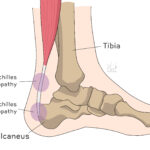

[doctormodu]1 아킬레스건염 종류 Achilles tendinopathy classification

09 아킬레스건병증 Achilles tendinopathy